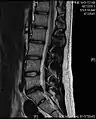

- Magnetic resonance imaging is the gold standard study for confirming a suspected LDH. With a diagnostic accuracy of 97%, it is the most sensitive study to visualize a herniated disc due to its significant ability in soft tissue visualization. MRI also has higher inter-observer reliability than other imaging modalities. It suggests disc herniation when it shows an increased T2-weighted signal at the posterior 10% of the disc. Degenerative disc diseases have shown a correlation with Modic type 1 changes. When evaluating for postoperative lumbar radiculopathies, the recommendation is that the MRI is performed with contrast unless otherwise contraindicated. MRI is more effective than CT in distinguishing inflammatory, malignant, or inflammatory etiologies of LDH. It is indicated relatively early in the course of evaluation (<8 weeks) when the patient presents with relative indications like significant pain, neurological motor deficits, and cauda equina syndrome. Diffusion tensor imaging is a type of MRI sequence used for detecting microstructural changes in the nerve root. It may be beneficial in understanding the changes that occur after herniated lumbar disc compresses a nerve root, and might help in differentiating the patients that need surgical intervention. In patients with a high suspicion of radiculopathy due to lumbar disc herniation, yet the MRI is equivocal or negative, nerve conduction studies are indicated.[44] T2-weighted images allow for clear visualization of protruded disc material in the spinal canal.

Example of a herniated disc at L5–S1 in the lumbar spine